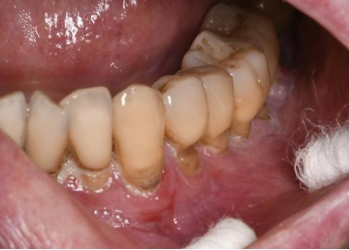

4. 牙周与牙齿

口腔症状共同导致了一个恶性循环:因疼痛而畏惧清洁,因张口受限而清洁不到位,因口干而失去唾液的自洁与保护,导致牙周炎症加重和龋齿5、11。口腔健康状况的急剧恶化,反过来又加重了感染风险和全身负担。

龋齿表现(图片源自陶人川教授团队)